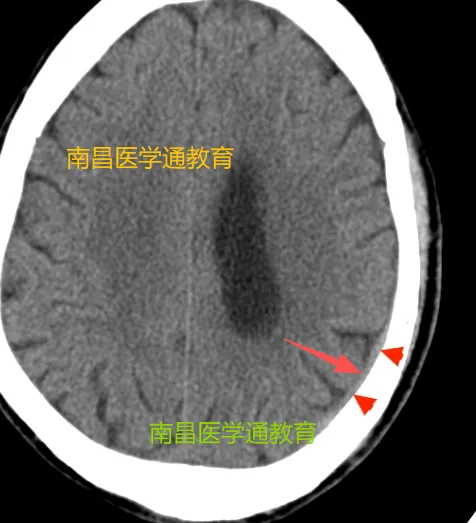

下图是大窗宽下显示的少量硬膜下血肿

是不是很难发现这个少量的硬膜下血肿。